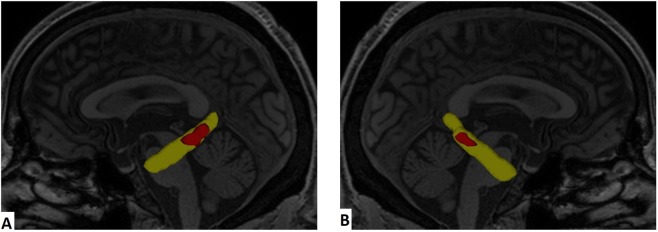

Linear SVM classification (parameter C equal to 1) based on all voxels inside the brain achieved an accuracy of 60% between AD and healthy controls, 57% between AD and MCI patients, and 47% between MCI and controls. Using feature selection, the set of voxels whose Fisher Score were higher than 1.0 reached the highest accuracy between AD patients and healthy controls at 80%, between AD and MCI at 77%, and between MCI and controls at 60%. The two biggest clusters of voxels whose Fisher Scores were higher than 1.0 when comparing AD and controls are inside the bilateral parahippocampal gyrus, as well as inside the bilateral cingulum in hippocampal formation (Fig. 1).

Figure 1.

Voxels whose Fisher Score (AD versus healthy controls) are higher than 1 (red) inside bilateral cingulum in hippocampal formation (yellow). (A) Left view. (B) Right view.